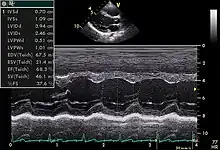

Echocardiogram in the parasternal long-axis view, showing a measurement of the heart's left ventricle

An abnormal echocardiogram: Image shows a midmuscular ventricular septal defect. The trace in the lower left shows the cardiac cycle and the red mark the time in the cardiac cycle when the image was captured. Colors are used to represent the velocity and direction of blood flow.